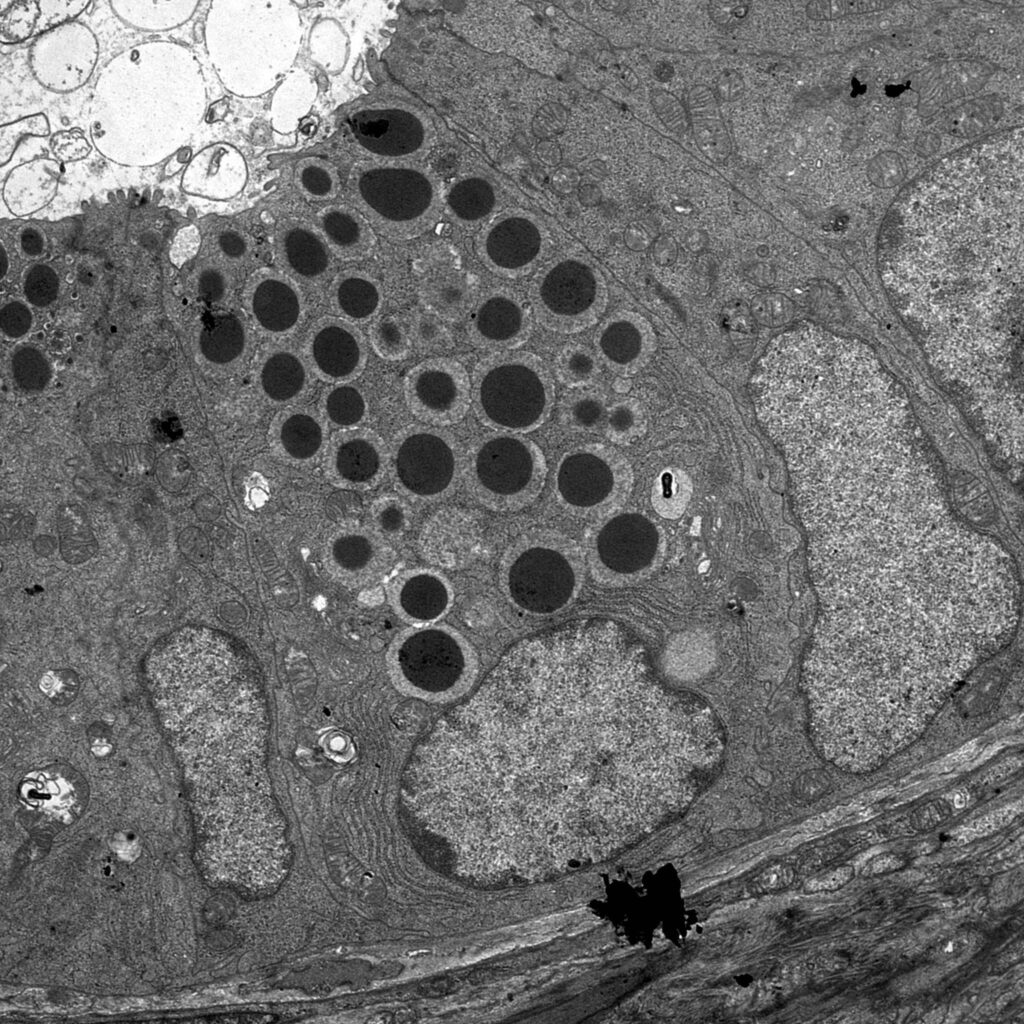

Die Rolle der Darmflora

Das Mikrobiom – die Gesamtheit aller Mikroorganismen, die unseren Darm besiedeln – spielt eine entscheidende Rolle für unsere Gesundheit. Bei Personen mit CED zeigt sich oft eine veränderte Zusammensetzung der Darmflora. Diese solche Dysbiose kann die Entzündungsprozesse im Darm verstärken und zur Entwicklung der Krankheit beitragen. Es ist jedoch noch unklar, ob die Veränderungen in der Darmflora eine Ursache oder eine Folge der Erkrankung sind.